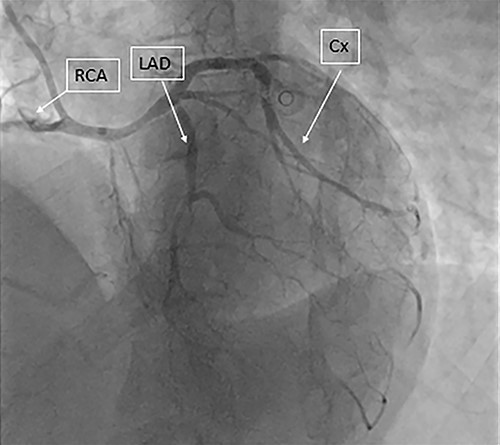

A previously fit and healthy 47-year-old man was admitted to his local hospital with delayed infero-lateral ST segment elevation myocardial infarction (STEMI). His surgical history was significant for correction of left forearm deformity since childhood. He had persistent left forearm contracture with significant atrophy in in left arm and left leg. He was treated medically at the time of presentation and transferred to our center for coronary angiography, which showed significant triple vessel disease arising from single right coronary ostium (Fig. 1). Transthoracic echocardiography showed ejection fraction of 40% with hypokinesia of inferior and lateral walls and trivial mitral valve regurgitation with no associated congenital defects. Computed tomography (CT) of the heart (Fig. 2) showed both left main and right coronary arteries arising from one single ostium in the anterior coronary sinus. Left main stem was seen passing between aorta and right ventricular outflow tract in sub pulmonic course. Left anterior descending artery (LAD) was short and had significant stenosis in its ostium. Magnetic resonance imaging (MRI) heart showed no evidence of any cardiovascular congenital anomalies with situs solitus and levocardia with normal arterial trunk connection. As his coronary anatomy was unsuitable for stent insertions, he was referred for coronary artery bypass graft (CABG) surgery. Patient underwent CABG through median sternotomy with left internal mammary artery anastomosed to LAD, reverse saphenous vein graft anastomosed to obtuse marginal and reverse saphenous vein graft anastomosed to posterior descending artery. LAD was deep intra myocardial. Procedure was performed with cardiopulmonary bypass (CPB) and cardioplegic arrest. Patient was weaned from CPB with minimum doses of norepinephrine and was extubated 12 hours post operatively. He was discharged home uneventfully on fifth postoperative day with no complications. On follow-up at 12 months, he remained well with no symptoms.

Coronary angiography showing the three coronary arteries arising from single ostium with short LAD and occluded RCA and circumflex artery is shown.